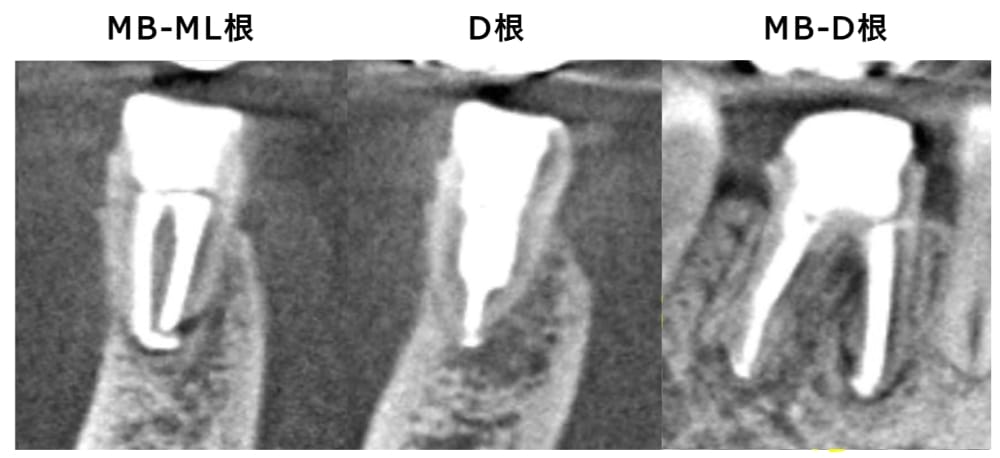

レントゲン・CT画像にて、右下第一大臼歯の根尖部に、明瞭な骨吸収像が認められます。来院時には根管治療の途中の状態でしたが、内部に虫歯が残っており、感染源が取り除けていない状態でした。急性炎症に対して確実な即効性がある治療はありませんが、最大限感染を除去し、細菌の侵入を防ぐことを第一に応急対応を行いました。

術後6ヶ月が経過時点でのレントゲン・CT画像では、もともとはっきりと写っていた根の先の黒い部分は消失し、骨の回復が認められます。痛みも全くなくなり、治癒していると判断し、最終補綴(かぶせもの)を行うことになりました。